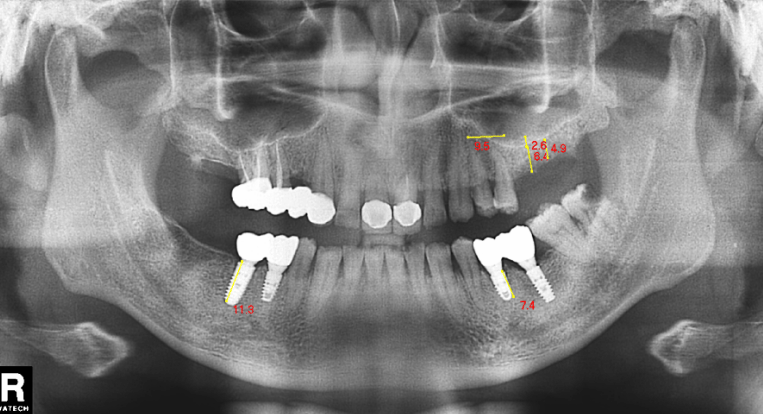

种植牙一般包括人工牙根,即种植体、基台、牙冠。

纯钛植体一般分为四级钛和五级钛。

在纯钛材质中,一级、二级、三级钛一般杂质多,纯度低,现在基本已经不用了。临床用的较多的又分为四级钛、五级钛。四级钛的,比如仕诺康种植牙、瑞士ITI种植体。五级钛的纯度更高些,强度更高些,韧性略差。比如,美国杰美种植体、法国安卓健种植牙。

这款种植体强度比纯钛的更高,种植体直径可以做到更小。在一些情况,患者可以避免做骨增量手术。